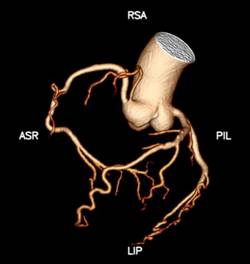

1、心脏检查时无需屏气,无需服药控制心率

Apex CT拥有160mm超宽体探测器,旋转一周仅需0.28s,即可以在一个心动周期内完成整个心脏的扫描。患者无需提早一小时来服药控制心率,高心率、房颤室颤、无法配合呼吸的患者都能在自然状态下接受检查,并通过高能量子球管使用的低kV高mA的扫描模式,在降低对比剂速率、用量和辐射剂量的同时,还能提高组织对比度,得到更高的密度分辨率,显示出更清晰的病灶。